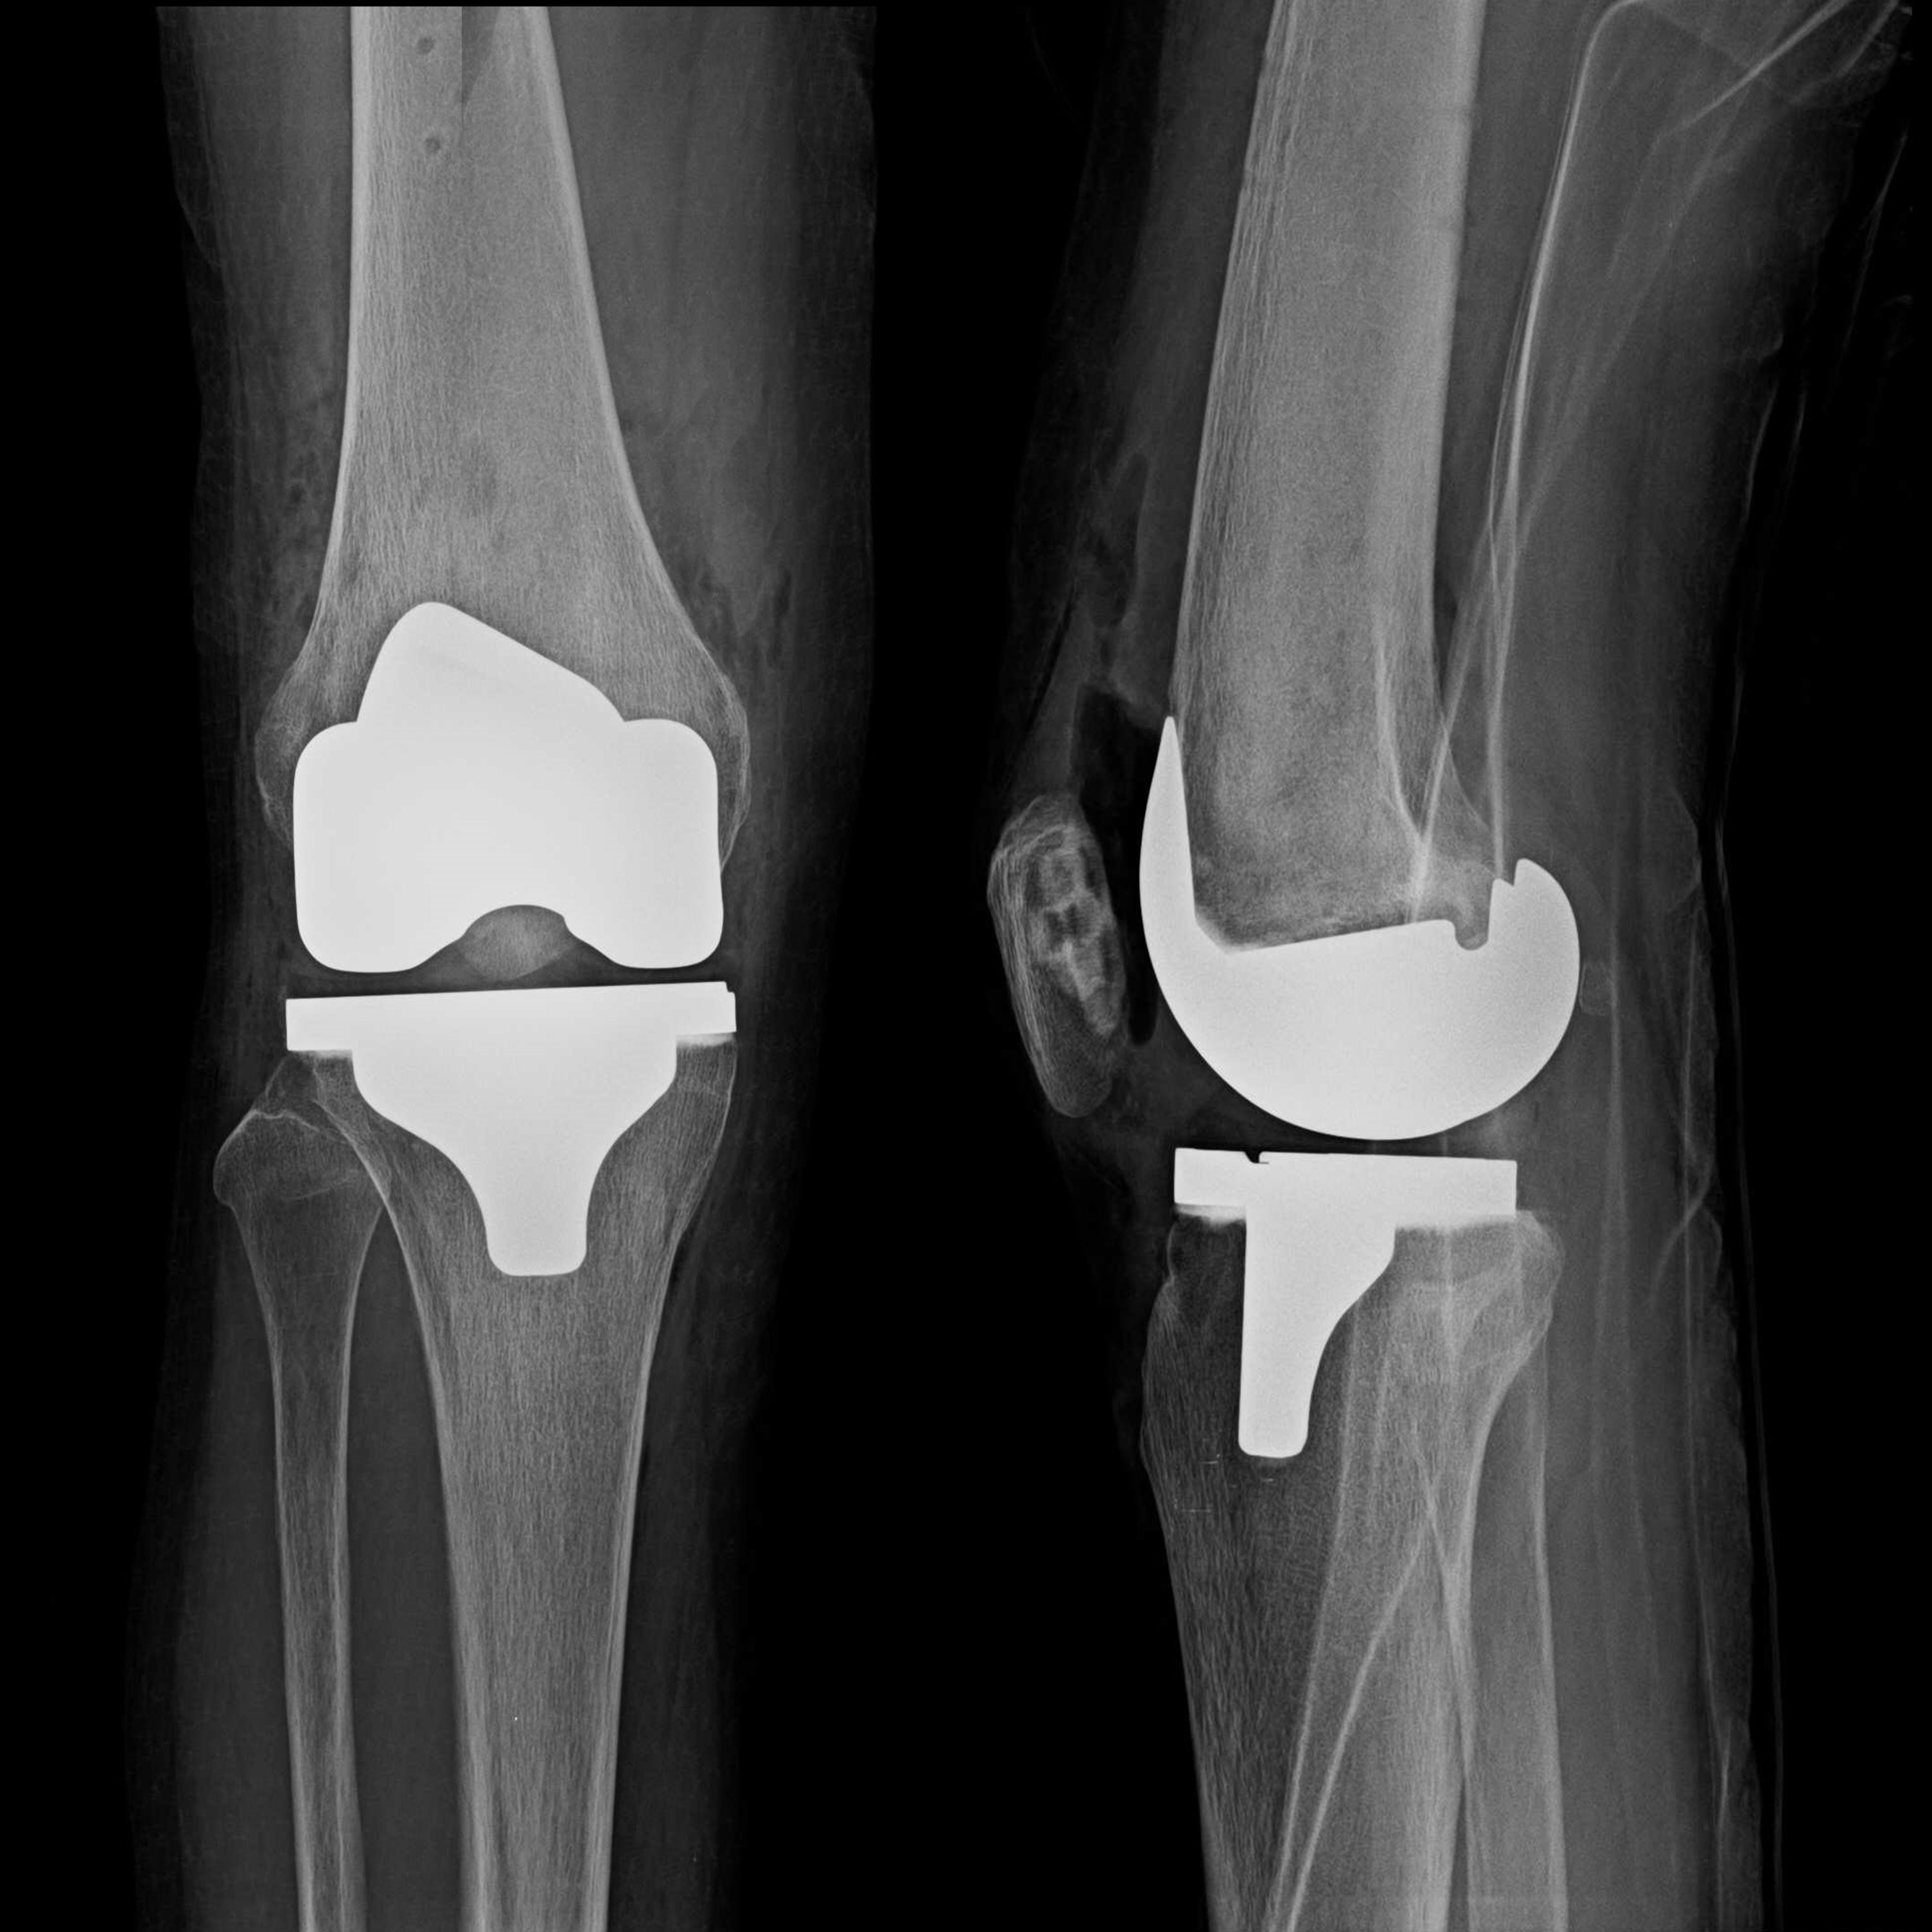

機器手臂手術 首頁 案例分享 膝關節手術 機器手臂手術 蔡女士 78歲 術前 術後 陳女士 70歲 術前 術後 術前 術後 ANGEVINE女士 73歲 術前 術後 U.S.A Mark 73歲 術前 術後 藍女士 78歲 術前 術後